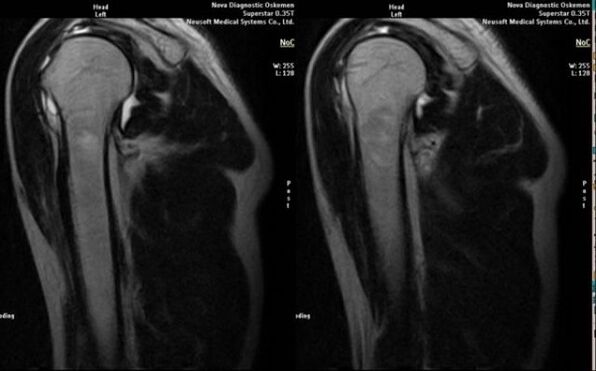

- magnetic resonance and computed tomography;

Signs that directly indicate the development of arthrosis include the appearance of significant narrowing of the joint space, sclerosis of the subcartilaginous structure, thinning of the chondrocyte layer itself, the appearance of osteophytes and the deposition of salt crystals in the intra-articular fluid.